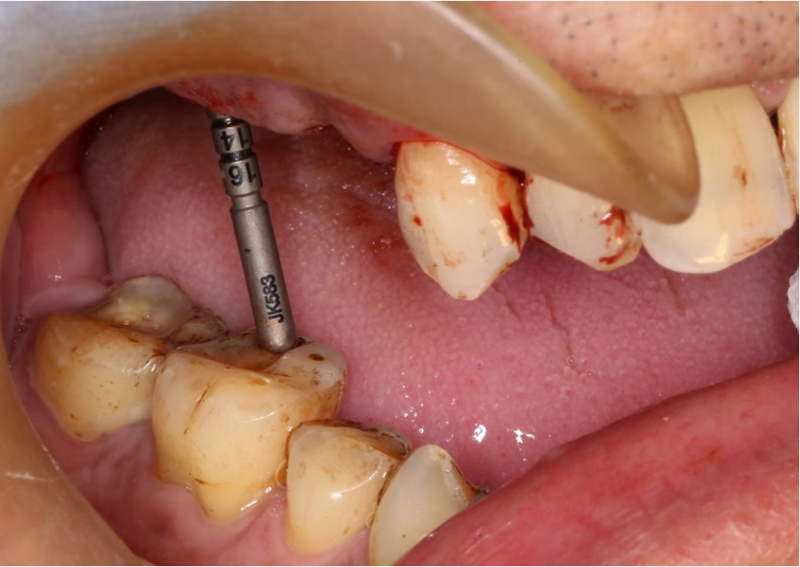

®按照術前方案進行備洞及植體植入,醫(yī)生可以通過屏幕軟件引導對手術中植入點、角度、深度實時追蹤

®對植體深度及方向進行確認